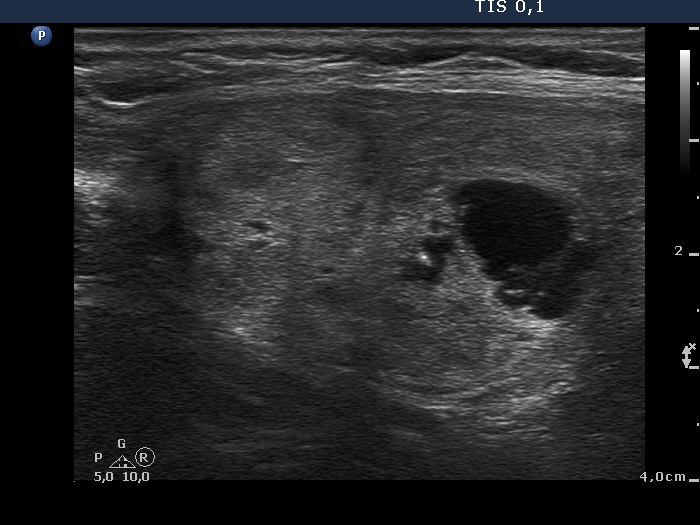

Clinical presentation: A 77-year-old woman was referred for evaluation of a nodular goiter which has been known for years. A mass was found in the left upper mediastinum on CT scan 6 weeks ago on evaluation of pneumonia. The patient had no neck complaints.

Ultrasonography. The thyroid was enlarged and had numerous nodules of different echogenicities. From an oncological point-of-view, the nodule located in the isthmic part of the left lobe was the most important. The lower pole of both lobes could be visualized on ultrasound examination.

Aspiration cytology of the nodule in the isthmic part of the left lobe resulted in benign cystic-colloid goiter.